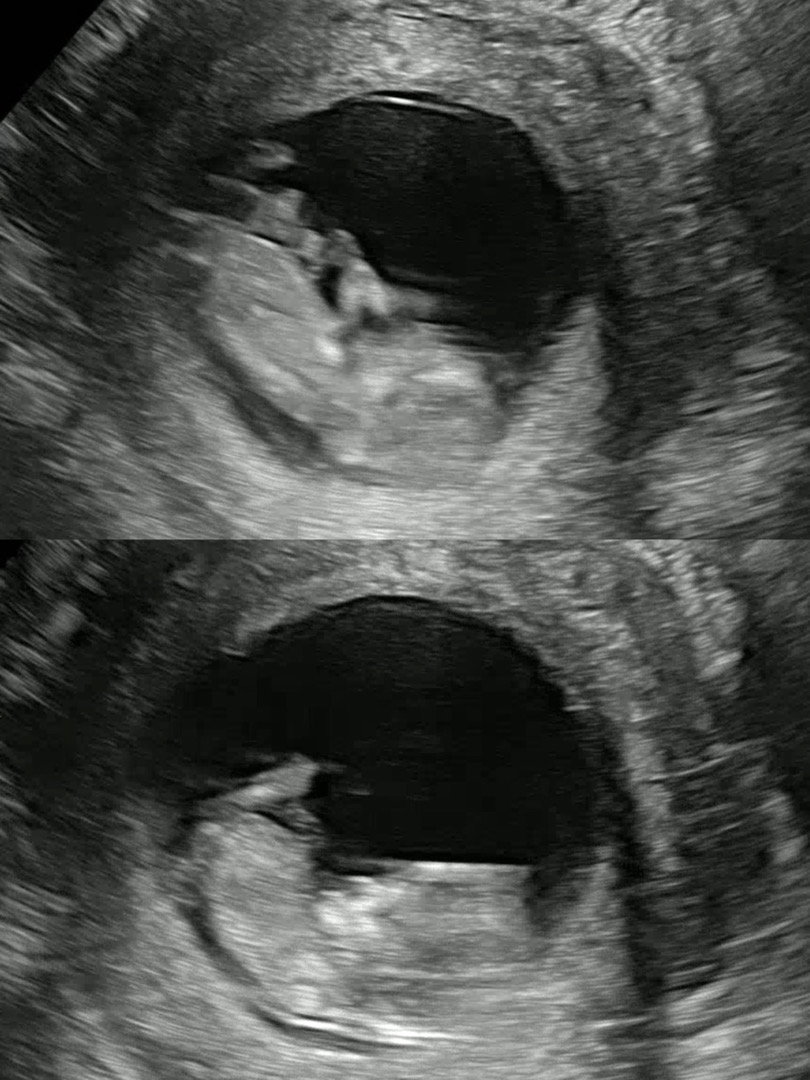

11주차 각도법 고수님들 부탁드려요🥹

한달뒤에 병원가면 알수있다지만 벌써부터 궁금한 엄마 마음입니다🤣 전 아무리 봐도 모르겠어요ㅠㅠ 각도법 고수님들 혹시 보이실까요?!! 소중한 댓글 부탁드립니당!!!ㅎㅎ